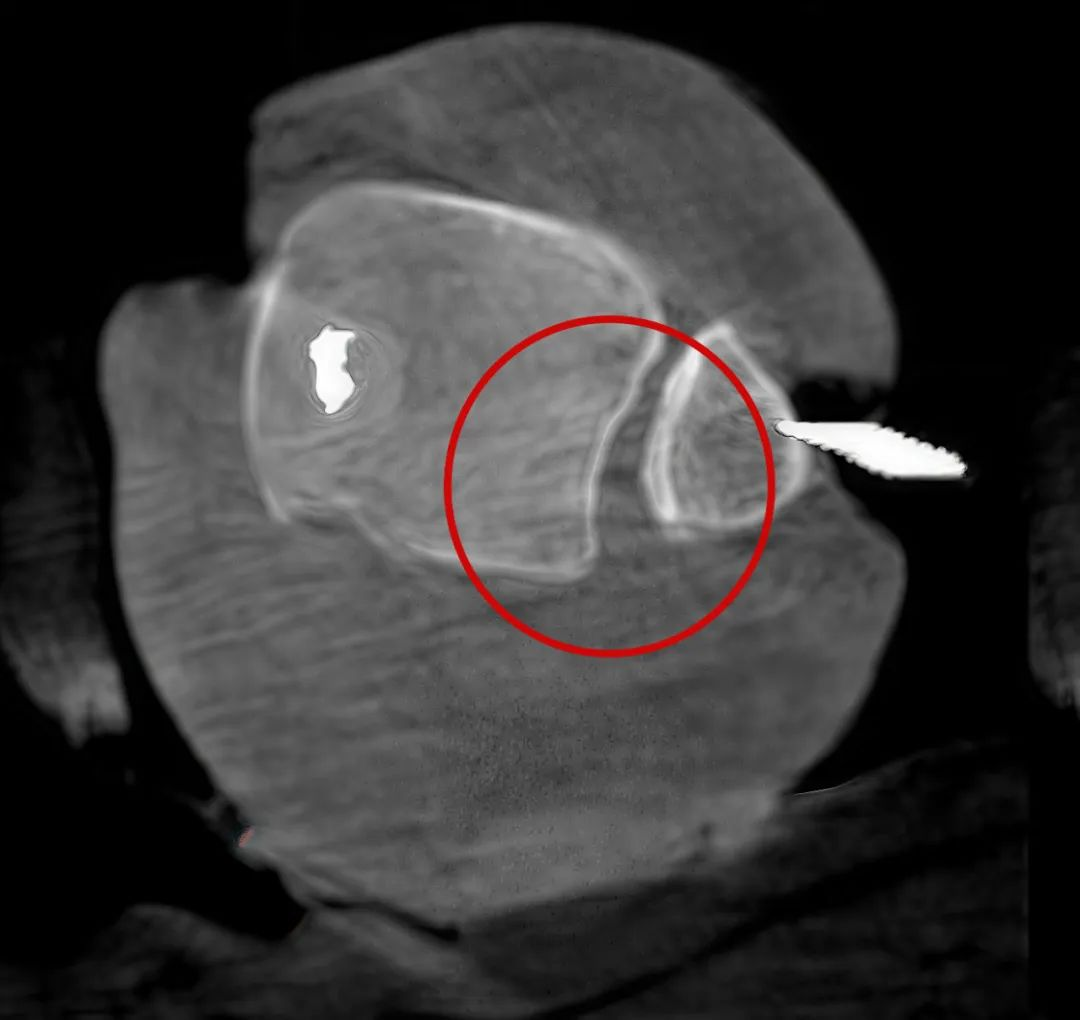

病例1:右侧股骨远端骨骺骨病(13岁)

二维影像看不到病灶点

三维切面影像可以看出病灶点